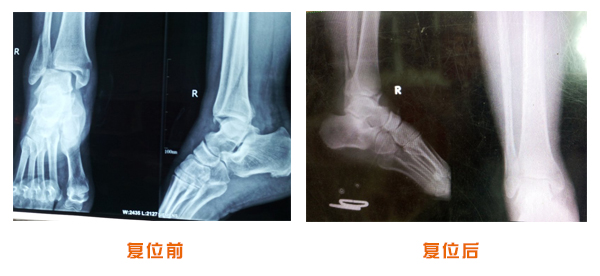

復位前后對比

踝關節脫位骨折治療前后對比